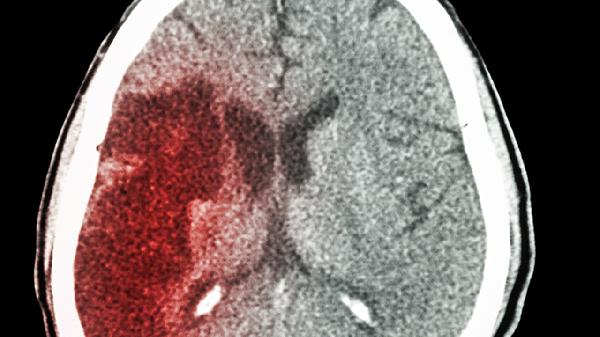

改善脑供血不足是一个综合管理过程,药物治疗需在神经内科医生全面评估后个体化制定方案。除了遵医嘱规律服药外,患者应保持健康的生活方式,包括低盐低脂饮食、控制体重、戒烟限酒、进行适度的有氧运动如散步或慢跑,并积极管理高血压、糖尿病等基础疾病。定期复查,监测血压、血脂及药物不良反应,对于稳定病情、预防脑卒中至关重要。切勿自行购药或更改治疗方案。